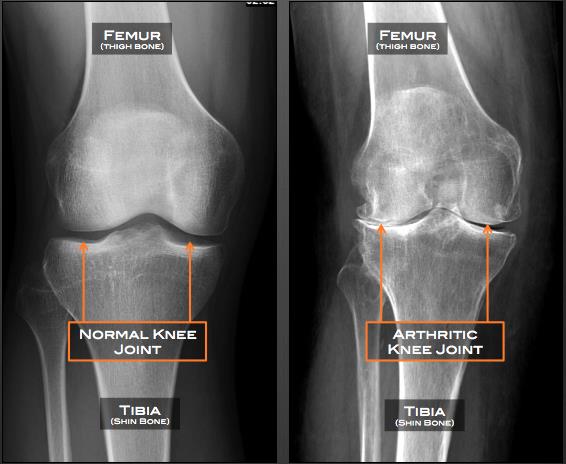

Knee Osteoarthritis (OA) is a medical condition that usually affects individuals middle-aged and older. As one of the most frequent types of arthritis, it involves the breakdown of the cartilage in the knee, leading to pain, stiffness, and mobility challenges.

Diagnosis involves a physical examination, medical history, and imaging tests, including X-rays and MRI. Your doctor may also order lab tests to rule out other conditions.